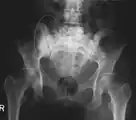

X-ray: Bone cancer in hip, spread from prostate cancer. -

X-ray: Bone cancer in hip, spread from breast cancer.